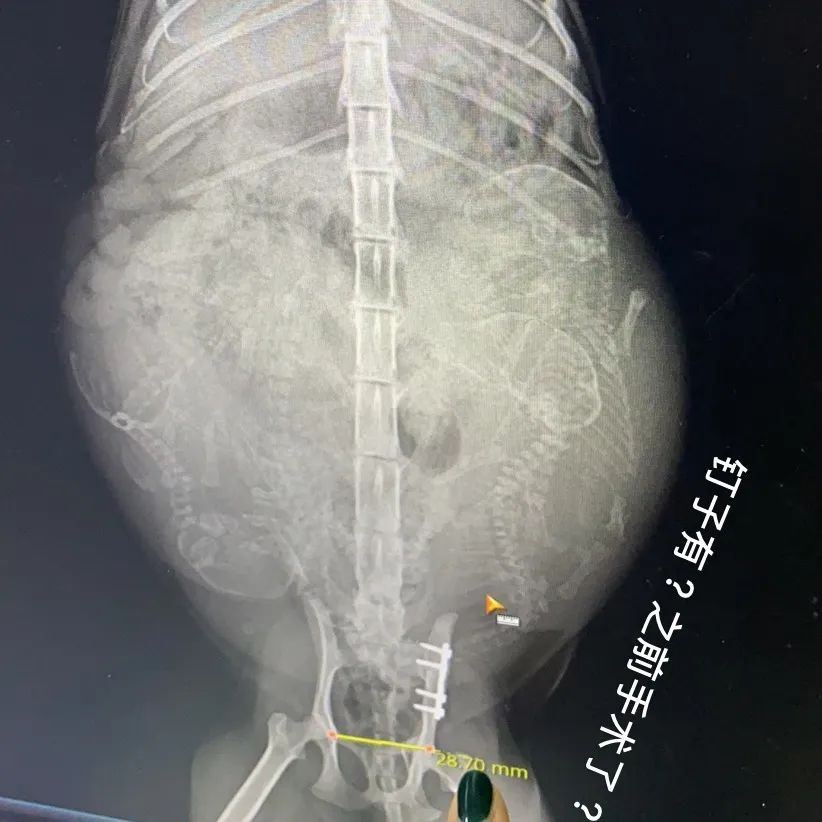

我身在的黄浦区豫园街道,当时还没封闭。虽然离嘉定很远,但还是决定马上出发。由于路途遥远,且嘉定区部分道路已被封锁,不确定是否能如时到达,种种权衡,主人决定先叫闪送电动车师傅把猫妈妈送往医院。但我想,如果是自己的猫出事了,没人陪,肯定很担心,且涉及不止一条生命,于是便转道去医院。到达后,医生正在为猫妈妈拍片,说肚子里面还有四只小猫,两只生命迹象微弱,猫妈妈也出现了应激,需要马上麻醉剖腹产。但医生不能保证生出来的小猫一定能活着。在主人同意微信看过手术协议书后,医生马上开始了手术。最后猫妈妈顺利产下四只小猫并保住了自己的性命。由于家中还有一只白天出生的小猫等着猫妈妈的奶水,不能住院,医生便开了消炎药,等妈妈醒来稳定后,让另一位后赶到的嘉定志愿者小姐姐把她送上专车,运回主被人封闭的小区。